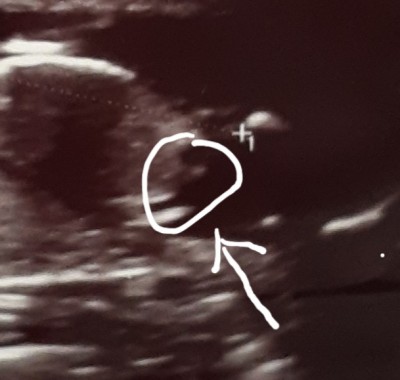

Kizlar Bi bakın erkekmi cikinti var

Pipi ye benzettim ben ama kordonda olabilir canım çok yakın çekim neresinin ölçümü bu

Bu normal fotografi ben fark ettim bugün ikizlere hamileyim ikisi kiz dedi bunu görünce acaba yanilmami oldu dedim

(4,419 puan) tarafından

Olabilir canım biraz daha buyuduklerinde daha net belli olur cinsiyetleri

Bugun 17+4 gunluk olduk bayram sorna tekrar gidicem bakim ne olucak

Kaç haftalık kuzum büyük ihtimal erkek kızda o çizdiğin yer hamburger dibi gözükür ❤️

erkek aynen